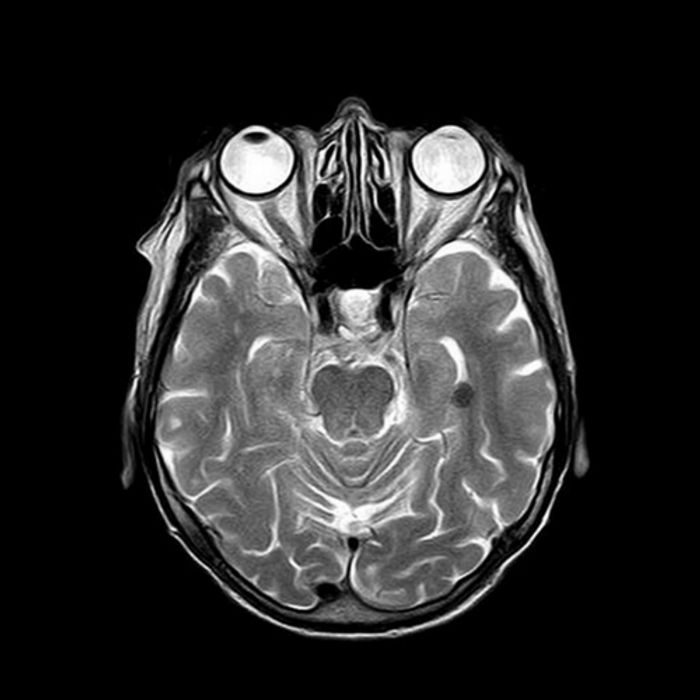

Brain Mri Axial Flair Slices Performed 1 Month After Stroke Disclosing Download Scientific Diagram

Brain Magnetic Resonance Imaging Performed 21 Years After Stroke Download Scientific Diagram